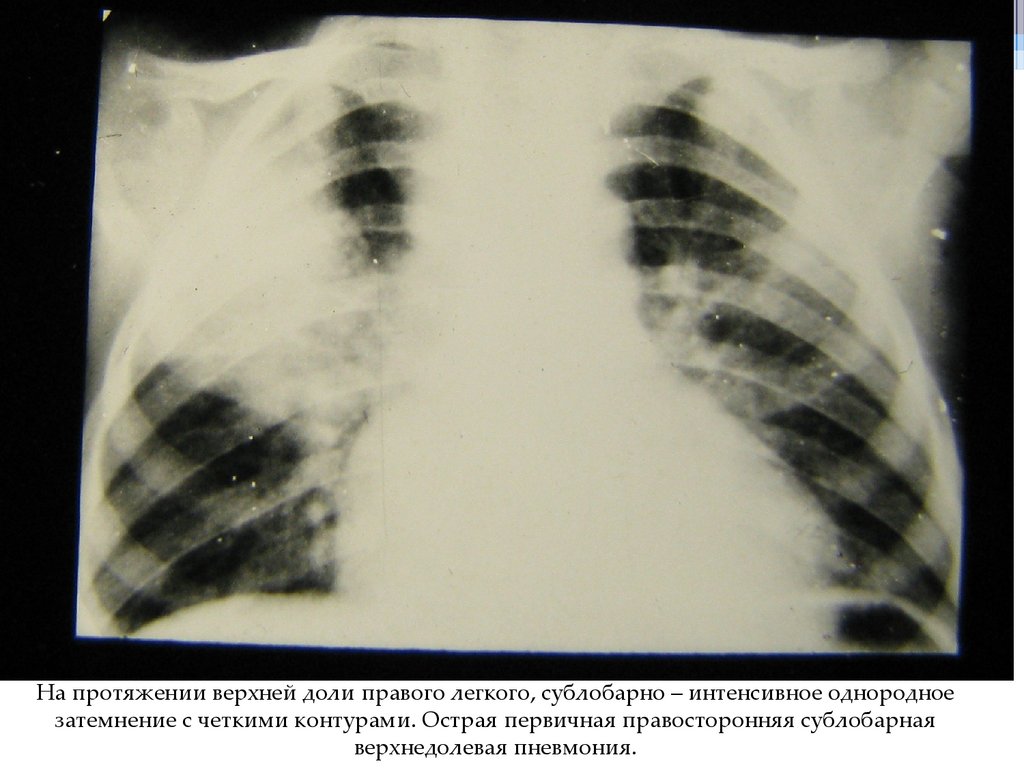

На протяжении верхней доли правого легкого, сублобарно – интенсивное однородное

затемнение с четкими контурами. Острая первичная правосторонняя сублобарная

верхнедолевая пневмония.